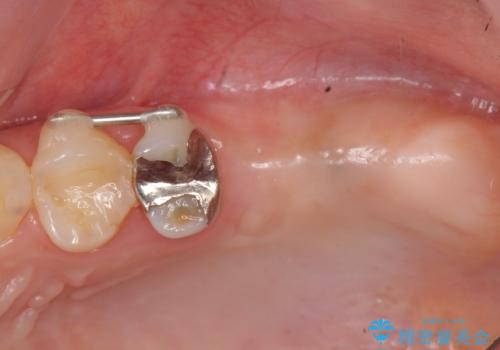

インプラントの仕上がりを見越して、ただ埋入するだけではなく長期的な予後を見込むには清掃のしやすい環境を整備することが大切です。

今回は大きく吸収してしまった歯槽骨をしっかりと造成することで、歯間ブラシを行いやすいインプラント周囲環境を整備することができました。